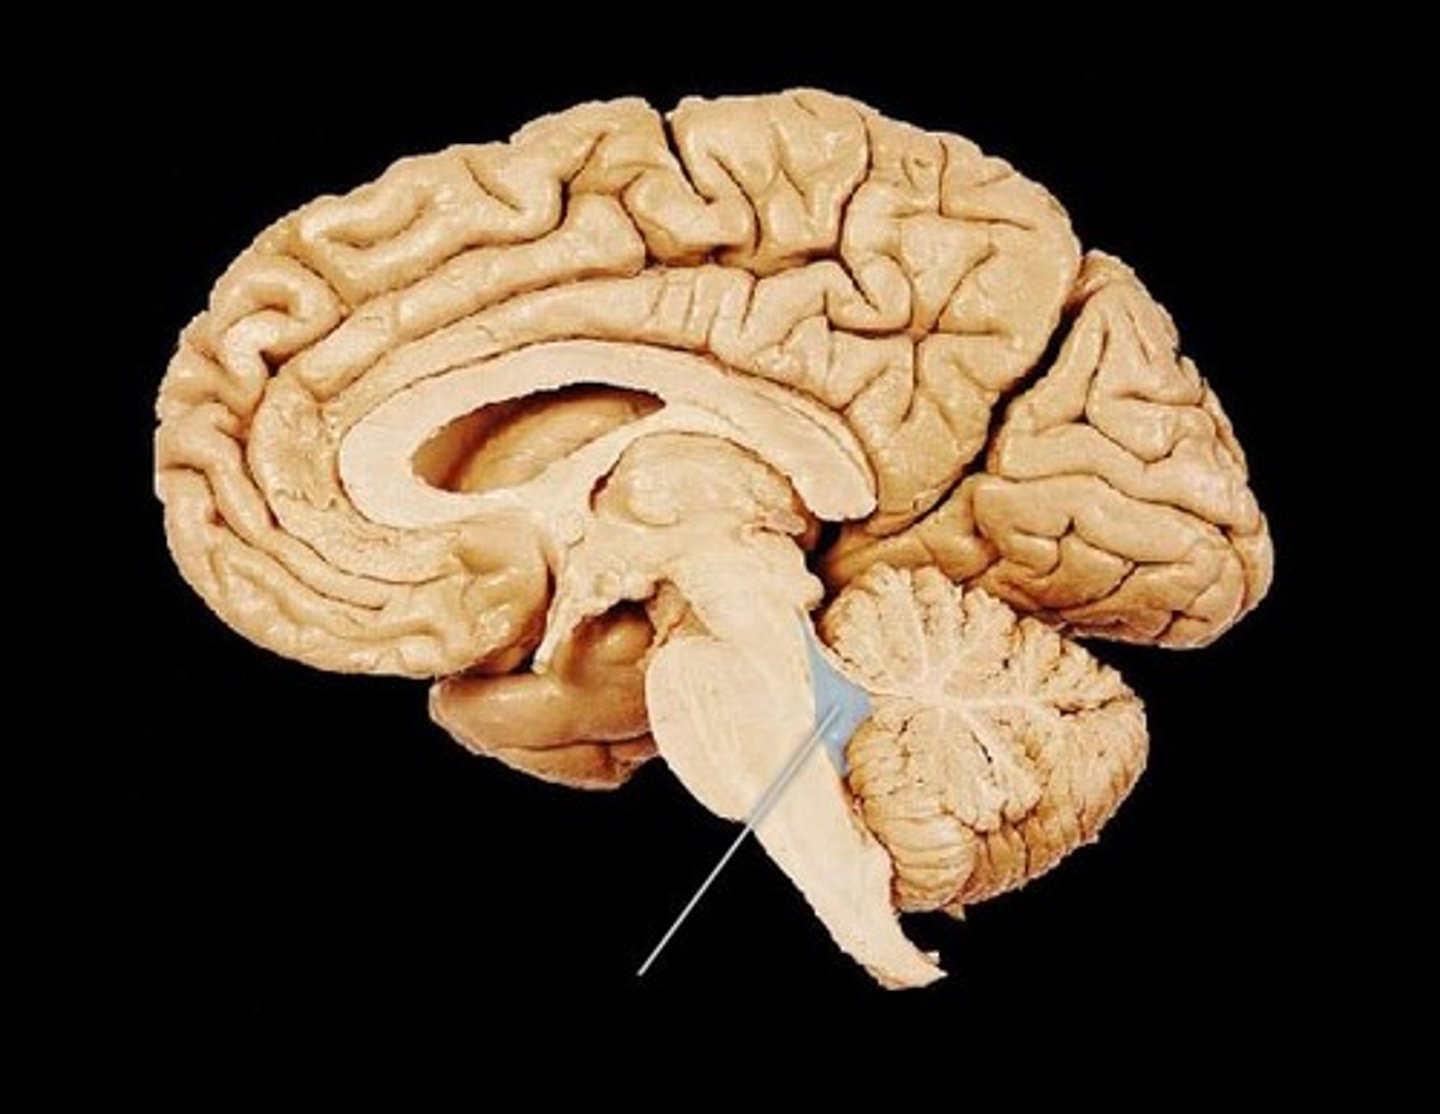

Arbor Vitae

The cerebellar white matter, so called for its branched, tree-like appearance. In some ways it more resembles a fern and is present in both cerebellar hemispheres. It brings sensory and motor information to and from the cerebellum.

Cerebellum

A region of the brain that plays an important role in motor control. It may also be involved in some cognitive functions such as attention and language, and in regulating fear and pleasure responses, but its movement-related functions are the most solidly established.